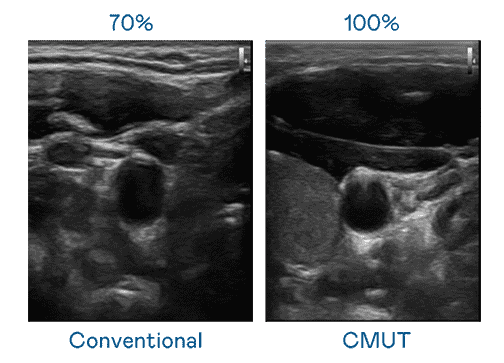

CMUT 技术是一种用电容式微机电元件来产生超音波讯号的技术。。。与传统 PZT 压电式技术相比,,CMUT 频宽增加 30%,,,,更宽频的超音波讯号让影像解析度大幅提升,,是实现高影像品质医疗超音波扫描、、、、促进精准医疗发展的关键技术。。。。

大频宽带来超清晰影像

超音波影像的解析度高低,,,,首先取决于探头能发出的讯号频宽。。。。银河集团 CMUT 可提供高清晰的超音波讯号,,,,提供高频宽、、高灵敏度、、、、影像纹理细节更高的超音波影像,,,,协助医护人员缩短影像判读时间及利用精准的医疗影像进行诊断。。。。